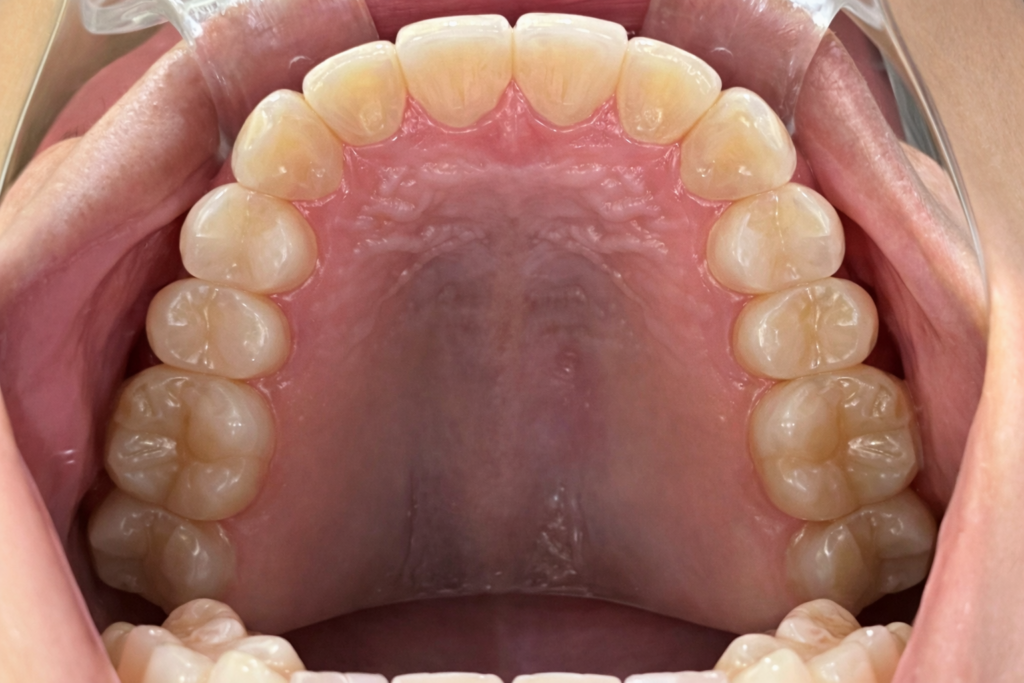

叢生の症例3(マウスピース矯正)

| 年齢 | 10代女性、叢生、八重歯 |

| 主訴 | 八重歯、歯のガタガタ |

| 診断 | 叢生 |

| 治療方法 | 上下・マウスピース矯正(抜歯はしていません) |

| 治療期間 | 約2年 |

| 費用総額 | 1,100,000円(税込) |

| リスク・副作用 | 痛み/歯根吸収/歯肉退縮/後戻り など |

本症例では八重歯がかなり出ている叢生状態でした。

下顎前歯のガタガタも併せて治したいというご希望でした。

抜歯も検討しましたが、スキャナーによるシミュレーション、精密検査により歯列のスペースを確保しかみ合わせも意識しながら歯並びを整えるため、抜歯をしないで矯正治療を行いました。

思春期で難しいながらもマウスピース矯正で行い治療後は歯並びとかみ合わせが改善し、

見た目だけでなく歯磨きもしやすい状態になりました。